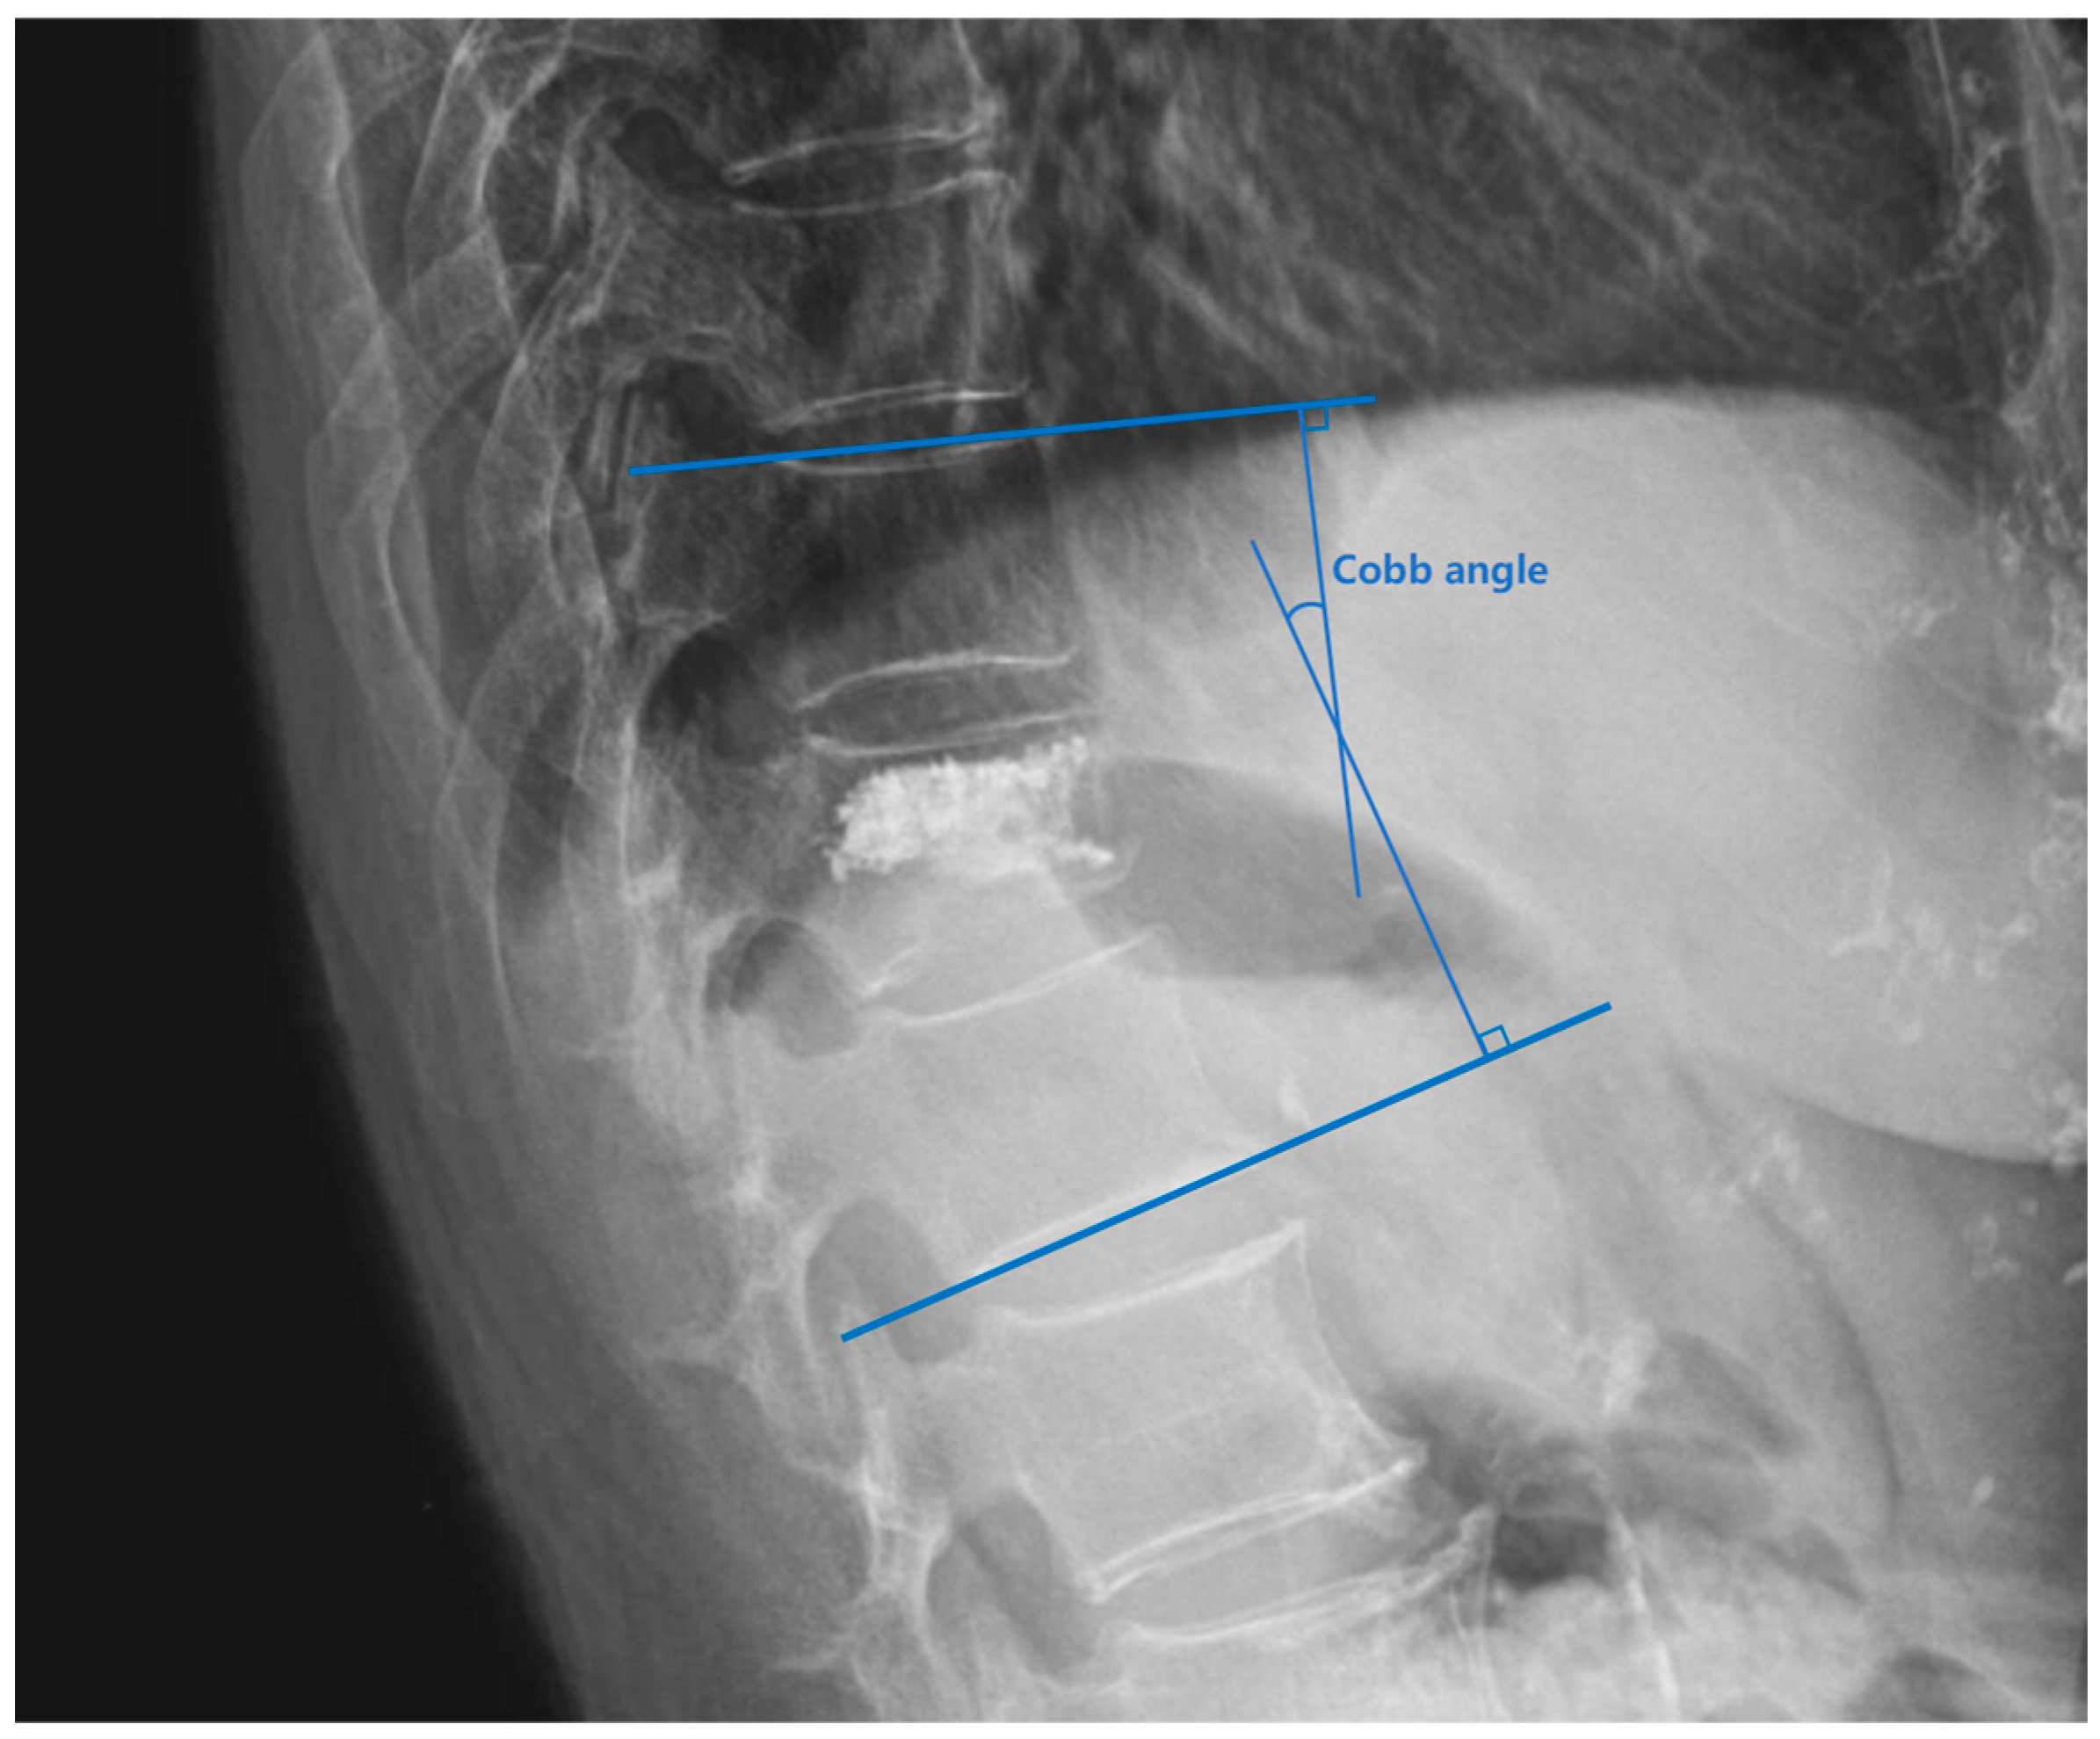

| Preoperative Cobb angle (°) | 14.000 (8.800, 19.000) | 14.650 (10.550, 21.775) | −0.988 | 0.323 * |

| Postoperative Cobb angle (°) | 12.700 (7.900, 18.400) | 7.500 (4.325, 13.150) | −2.495 | 0.013 * |

| Restoration of Cobb angle (%) | 4.368 (1.917, 12.050) | 43.316 (36.996, 56.754) | −5.474 | <0.001 * |